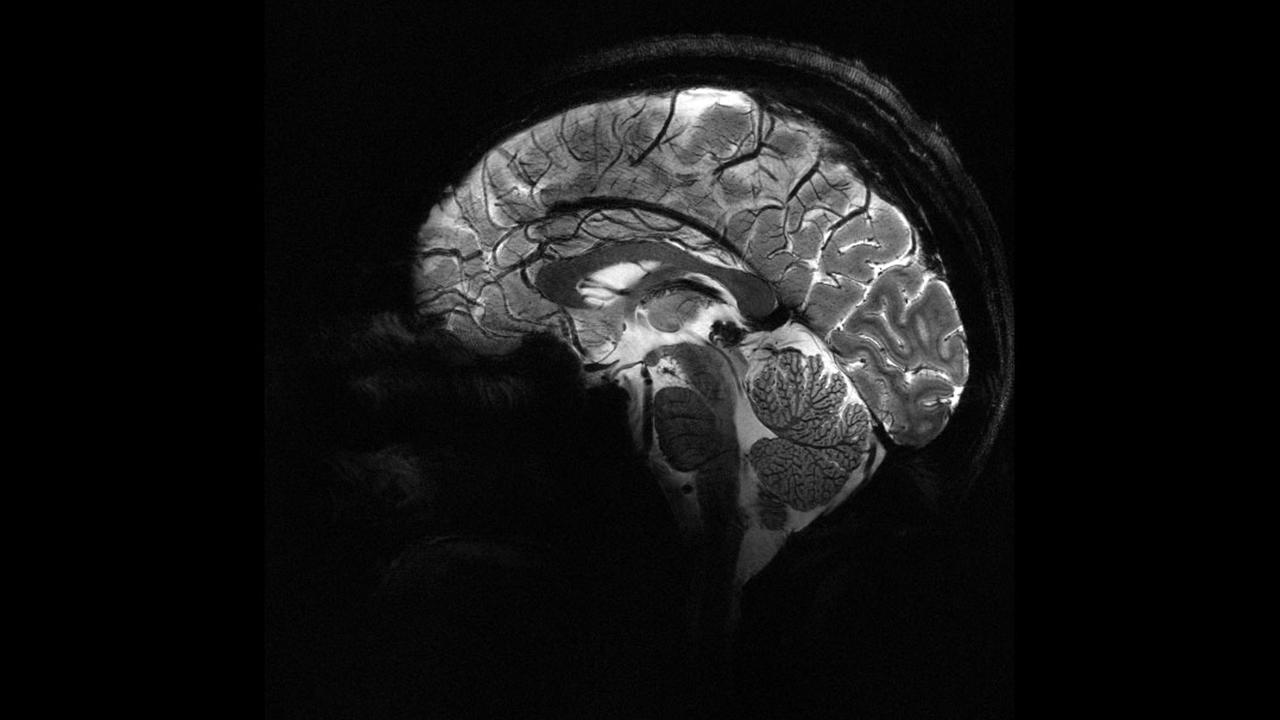

Beyindəki bəzi lezyonlar MRT görüntülərdə aşkar edilməyə bilir.

Tədqiqatçılar uşaq beyninin görüntüləri üzərində süni intellekt modelini təlimləndirərək, daha kiçik lezyonları aşkarlamağı bacarıb.

Araşdırmada daha əvvəl MRT nəticələri normal kimi qiymətləndirilmiş bu uşaqların 80 faizində əslində gizli lezyonların olduğu müəyyən edilib.

Süni intellekt aləti bir test qrupunda 94 faiz, digərində isə 91 faiz uğur əldə edib.